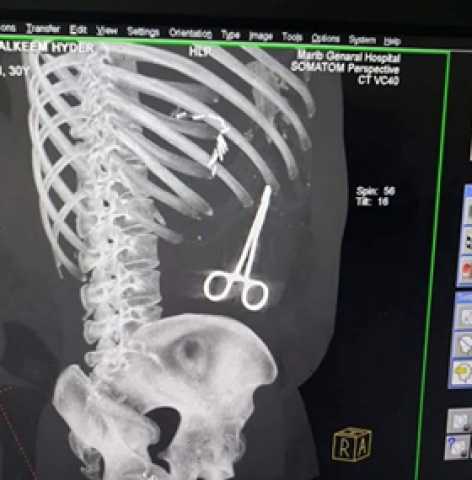

أفادت مصادر طبية يمنية، بأن أطباء هيئة مستشفى محافظة مأرب العام، تركوا مقصا في بطن أحد المرضى.

وذكرت المصادر، أن الأطباء بالمستشفى نسوا المقص أثناء إجراء عملية جراحية لأحد جرحى الجيش، وأن صورة الأشعة كشفت الحادث.

وأوضحت المصادر أن هيئة المستشفى فتحت تحقيقا عاجلا في الحادث، وسيتم رفع نتائج التحقيق، وإعلانها للرأي العام قريبا.